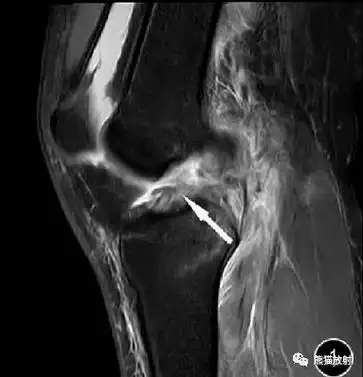

前交叉韧带损伤丨mri 征象_医学界-助力医生临床决策和职业成长